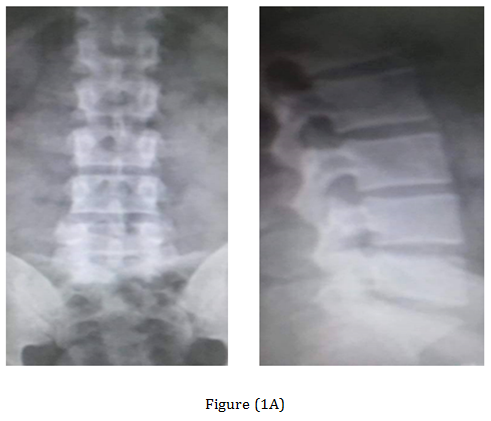

The post-operative Antero-posterior, lateral radiographs and dynamic views were used to assess the fusion mass at each level. The plain radiographs were obtained at 3 months, 6 months, 12 months, 18 months and 24 months to assess fusion status. Solid arthrodesis of the interbody space was confirmed by the presence of continuous bridging bone observed on the lateral radiographs, absence of lucencies around the cages, no cage migration or collapse and absence of halo around the screws. By Using this criteria, solid fusion was achieved in 18 patients (90%), whereas pseudarthrosis was documented in two patients. Low back and leg pain were completely resolved in 18 patients (90%) according to VAS (Table 1). All patients were rated minimal disability according to ODI (Table 2). The radiological outcome (Figure 1) showed solid fusion was achieved in 18 patients (90%), whereas pseudarthrosis was documented in two patients.

Figure 1 Case 3 with L.D.P L5-S1. (A) Preoperative radiograph anteroposterior and lateral views. (B) Preoperative MRI. (C) Post-operative radiographs anteroposterior and lateral views. (D) At the 18-months follow up anteroposterior and lateral views radiograph.